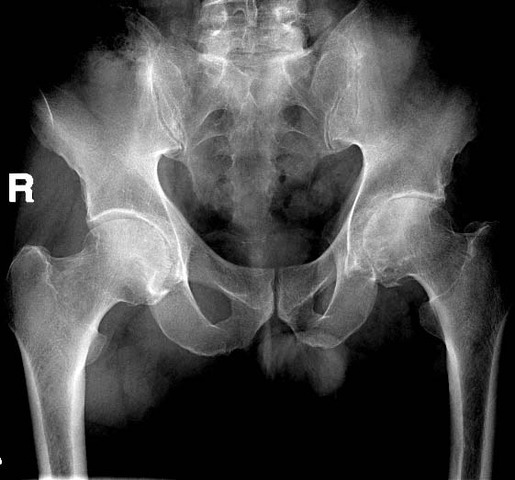

• hip surgery

hip surgery

i got my hip surgery in 1st grade. I had hip perthese disease in both hips but they said my left hip was worse. I had 56 stitches and a permanent scar. I had a half body cast for 8 weeks it sucked.